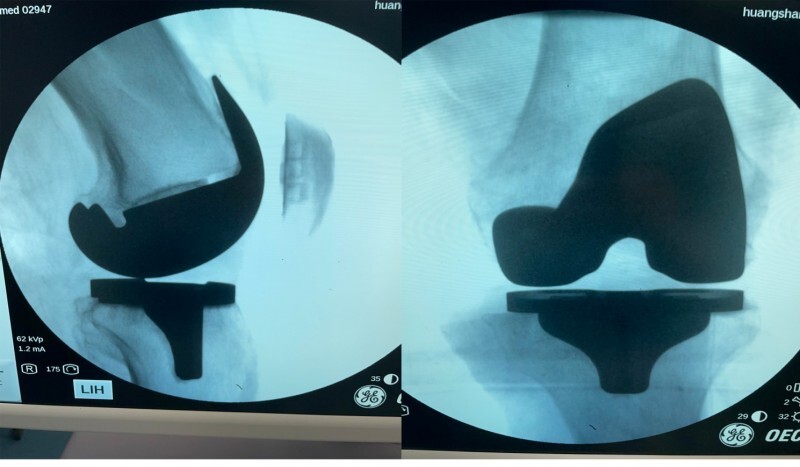

第3例:机器人辅助下左膝内侧单髁关节置换术

来自祁门的许某某在10年前就出现了左膝关节疼痛,期间多次就医,各种治疗也都尝试过,效果均不怎么理想。今年过完年,左膝关节疼痛加剧,已经严重影响生活质量,于是前来新晨医院就诊,检查后以“左膝骨性关节炎”住院治疗。

术中,经过机器人的准确定位,骨科手术团队的通力合作下,手术顺利,术后片子显示,假体植入位置准确,术后预期不错。

第4例:机器人辅助下全膝关节置换术

第四例患者是女性,55岁,情况和第一例手术类似,也是全膝关节置换手术,手术在机器人的辅助下顺利完成,目前患者情况稳定,正在恢复当中。